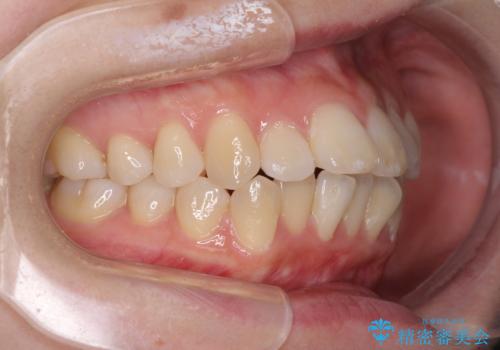

- 口元の突出感と口の閉じにくさを気にして来院された患者様です。

上下左右第一小臼歯4本を抜歯し、ワイヤー装置にて口元を引っ込めるよう矯正治療を行うこととしました。